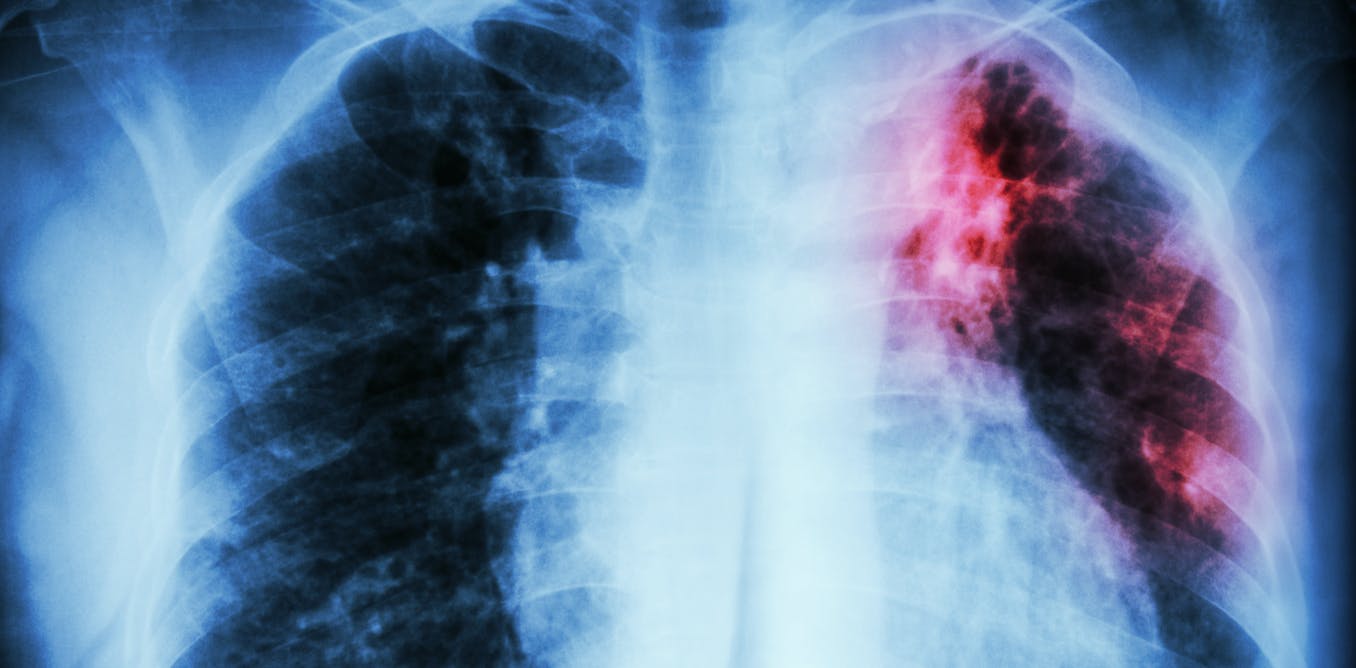

Bogotá, diciembre 18 de 2023 (Prensa Senado). En una iniciativa destinada a fortalecer el tratamiento y diagnóstico de la tuberculosis en Colombia, avanza un proyecto de ley en el Senado de la República. Con base en las estadísticas del Instituto Nacional de Salud, actualmente 20,000 colombianos luchan contra esta enfermedad, que afecta órganos como los pulmones, riñones y huesos, generando pérdida de peso y otras complicaciones. La capacidad médica para abordar esta problemática en muchos casos resulta insuficiente.